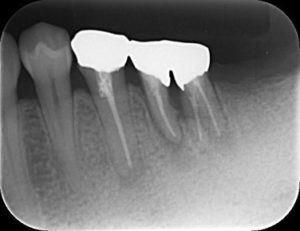

ブリッジの虫歯とかみ合わせをインプラントにて治療した症例 2019.07.17インプラントの症例虫歯治療の症例 ブリッジは虫歯になった後に気付きづらく、気づいたときには抜歯が必要になっている・・・という場合もあります。今回のケースはブリッジを早めに外したため残っている歯を引き出しインプラントは1本で治療ができ... 続きを読む

歯の根の治療と歯周病を同時に行った症例 2019.07.17歯周病治療の症例虫歯治療の症例 根治・歯周病治療・被せ物まで保険診療で行いました。治療期間:1年費用:保険適用内で3万程度リスク:抜歯になる場合がある。感染根処置歯の根の治療の終了セット後治療後抜歯の可能性が高かった歯が2年以上保... 続きを読む